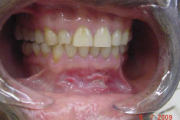

Aftoosne stomatiit

villikesest tekkinud haavand suu limaskestal